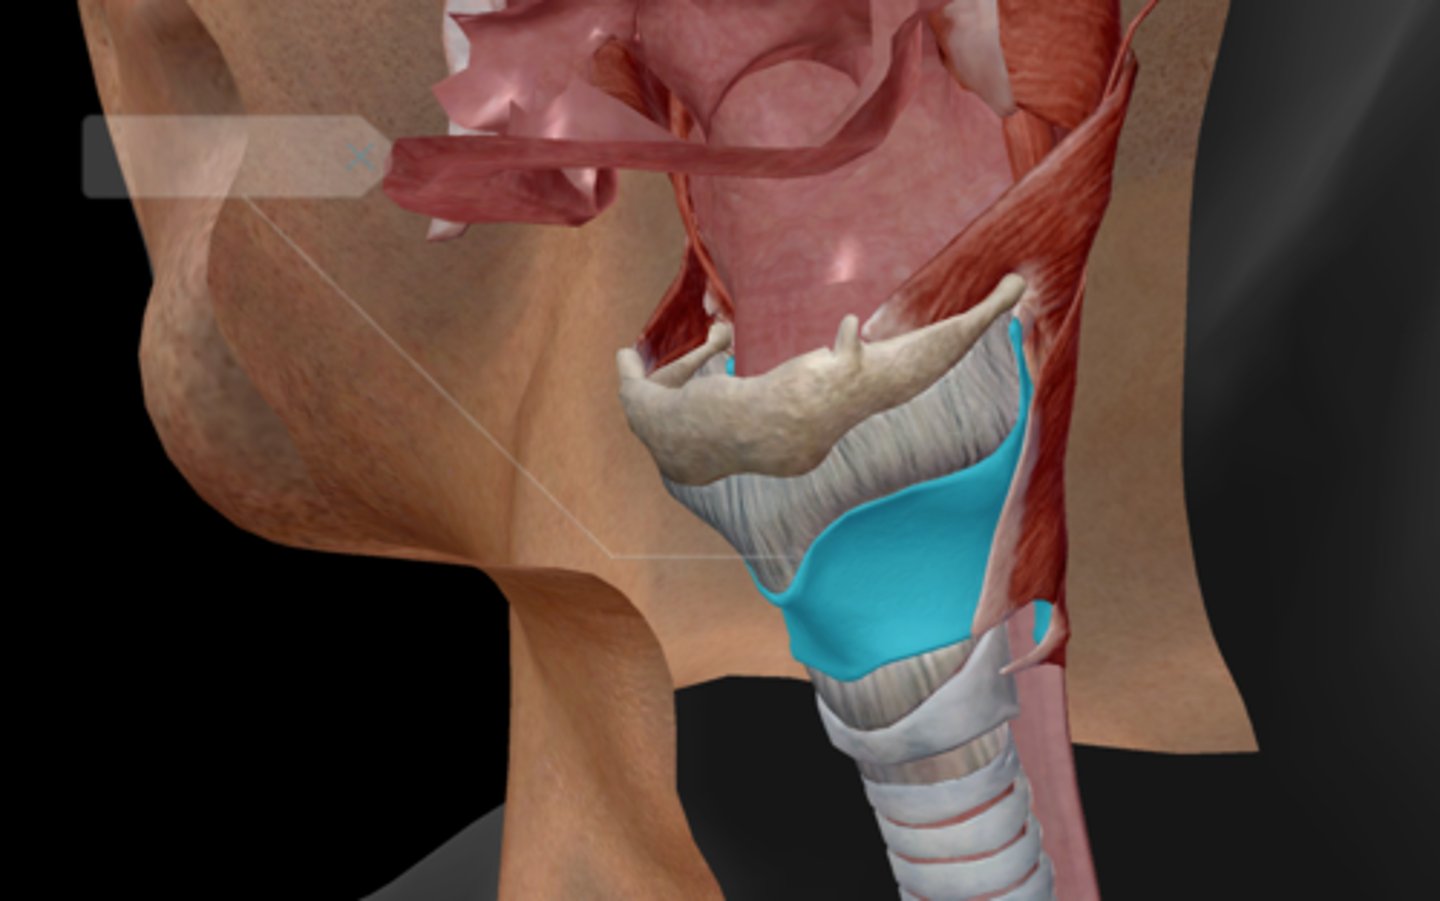

Nasopharynx

Oropharynx

Laryngopharynx

Larynx

Epiglottis

Thyroid cartilage

Cricoid cartilage

Trachea

Tracheal cartilaginous rings